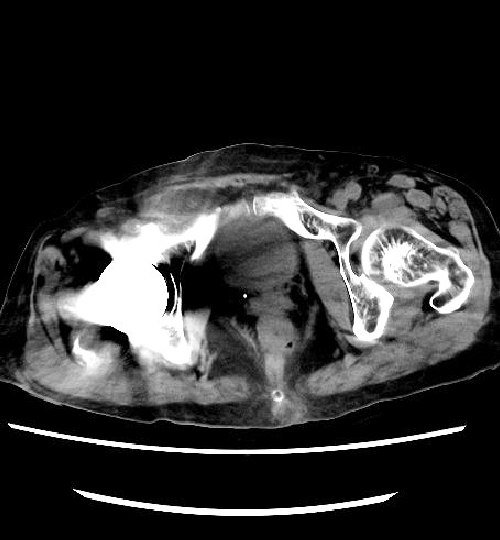

なお、従来の装置より実施しておりますCTCと称される短時間で苦痛の少ない大腸のCT検査も、変わらず対応しております。こちらも、より被ばく線量を低減した撮影ができるようになっております。